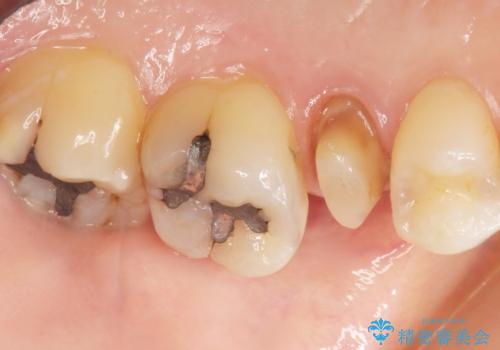

- 歯が欠けてしまったことを主訴に来院された患者様です。

欠けている奥歯(左上5)は失活歯で、保険内の銀の詰め物(メタルアンレー)で治療されていました。

金属の詰め物と土台を除去し、ファイバーコア(金属を使わない強くてしなやかな土台)を植立したのちセラミッククラウンによる補綴治療を行いました。

精査したところ、右上の奥歯(右上5)に根尖病変を認めたため、こちらは根管治療後にセラミッククラウンによる補綴を行いました。